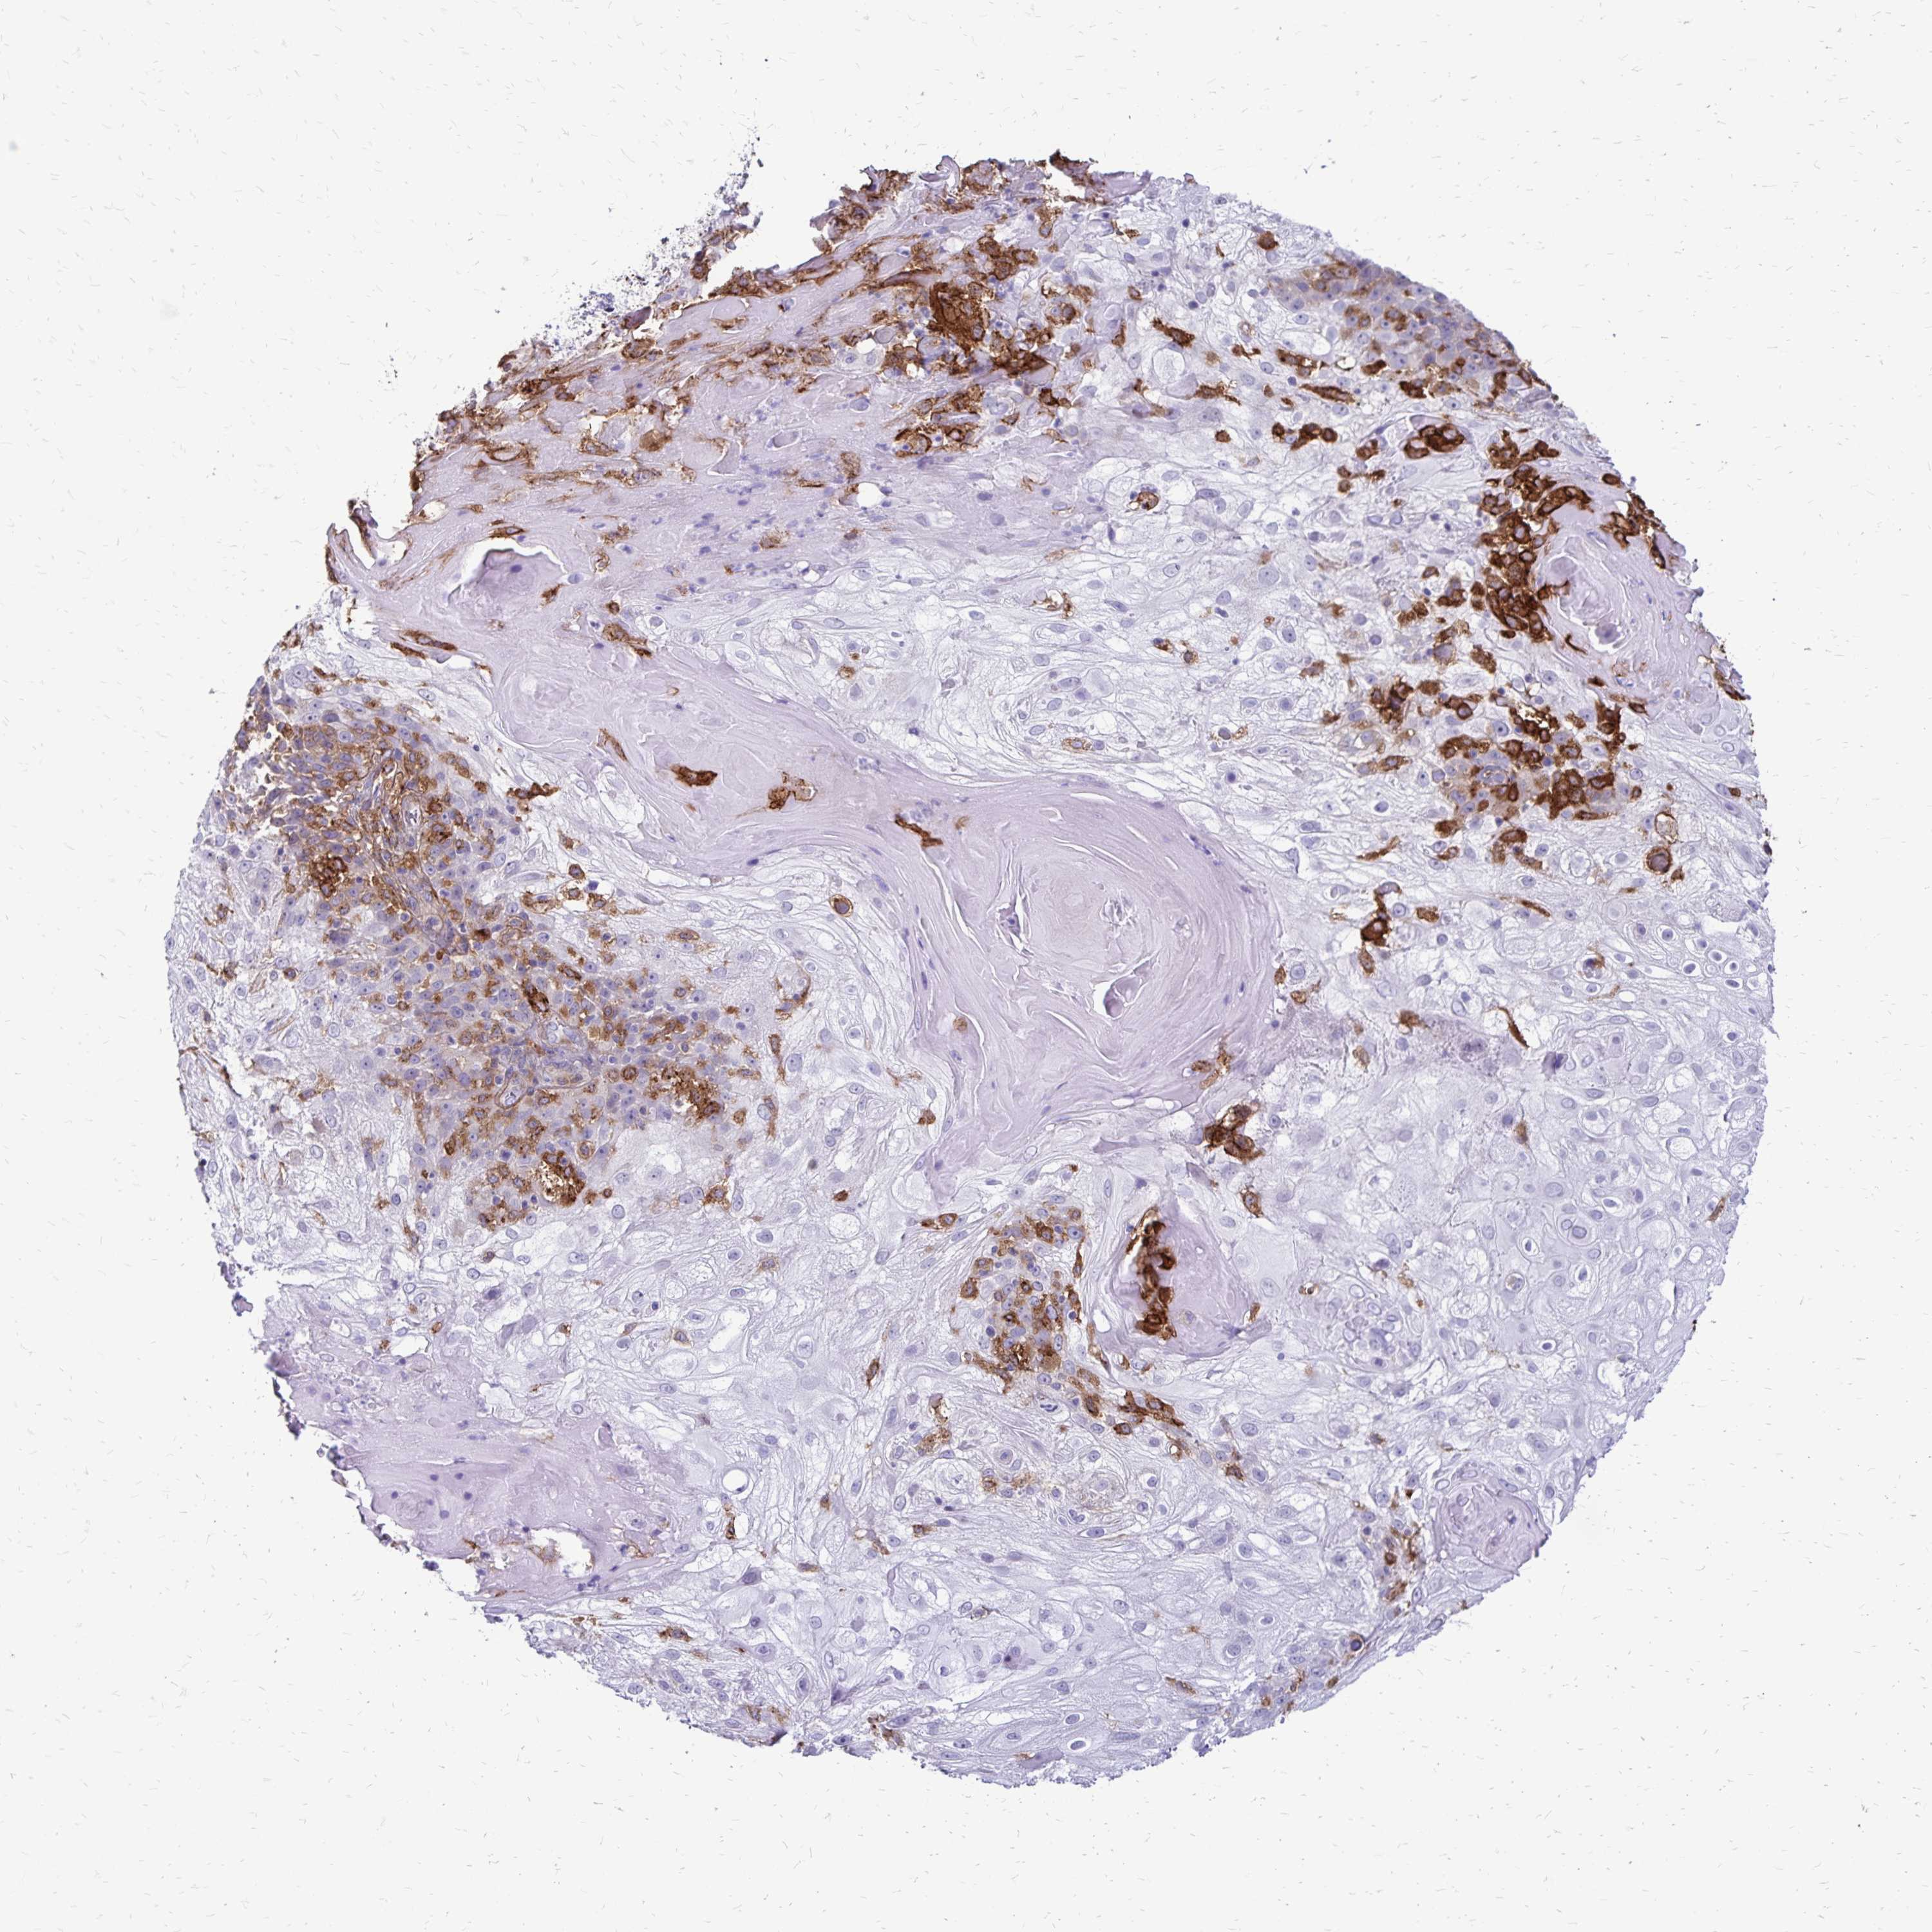

Basal cell and squamous cell cancer

SKIN CANCER - Protein expressioni

A mouse-over function shows sample information and annotation data. Click on an image to view it in a full screen mode. Samples can be filtered based on level of antibody staining by selecting one or several of the following categories: high, medium, low and not detected. The assay and annotation is described here.

Antibody stainingi

Antibody staining in the annotated cell types in the current human tissue is reported as not detected, low, medium, or high, based on conventional immunohistochemistry profiling in selected tissues. This score is based on the combination of the staining intensity and fraction of stained cells.

Each image is clickable and will lead to virtual microscopy that enables deeper exploration of all samples and also displays staining intensity scores, fraction scores and subcellular localization as well as patient and tissue information for each sample.

Antibody HPA055338

Antibody HPA056015

Staining

High

Medium

Low

Not detected

Intensity

Strong

Moderate

Weak

Negative

Quantity

>75%

75%-25%

<25%

None

Location

Nuclear

Cytoplasmic/membranous

Cytoplasmic/membranous,nuclear

Basal cell carcinoma

Squamous cell carcinoma, NOS